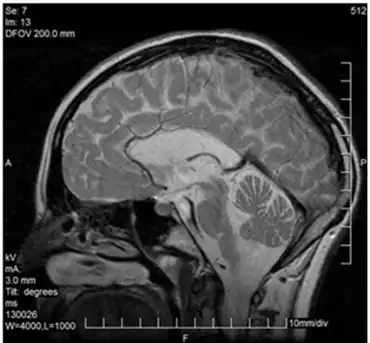

MRI

Leukoencephalopathy with vanishing white matter—corpus callosum is present but demyelinated

The MRI of patients with VWM shows a well defined leukodystrophy. These MRIs display reversal of signal intensity of the white matter in the brain. Recovery sequences and holes in the white matter are also visible.[4] Over time, the MRI is excellent at showing rarefaction and cystic degeneration of the white matter as it is replaced by fluid. To show this change, displaying white matter as a high signal (T2-weighted), proton density, and Fluid attenuated inversion recovery (FLAIR) images are the best approach. T2-weighted images also displaying cerebrospinal fluid and rarefied/cystic white matter. To view the remaining tissue, and get perspective on the damage done (also helpful in determining the rate of deterioration) (T1-weighted), proton density, and FLAIR images are ideal as they show radiating stripe patterns in the degenerating white matter. A failure of MRI images is their ineffectiveness and difficulty in interpretation in infants since the brain has not fully developed yet. Though some patterns and signs may be visible, it is still difficult to conclusively diagnose. This often leads to misdiagnosis in infants particularly if the MRI results in equivocal patterns or because of the high water content in infants' brains. The easiest way to fix this problem is a follow-up MRI in the following weeks. A potentially similar appearance of MRI with white matter abnormalities and cystic changes may be seen in some patients with hypomelanosis of Ito, some forms of Lowe's (oculocerebrorenal) disease, or some of the mucopolysaccharidoses.[2]